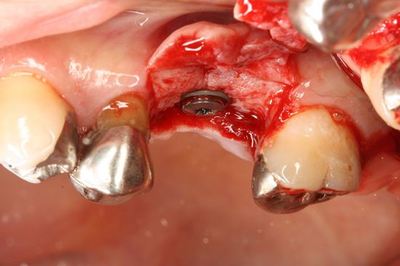

埋入を終えました。

![]()

挿入ジグをはずしました。

封鎖スクリュー高さ0.5mmで封鎖します。

封鎖しました。

封鎖スクリューで内部に組織や異物が入るのを防ぎます。